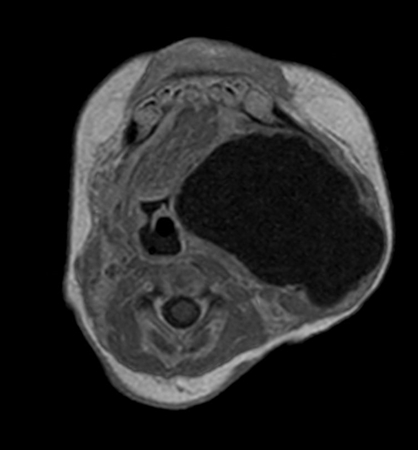

Axial mDIXON XD - T1w TSE (Water only)

Axial mDIXON XD - T1w TSE (In Phase)